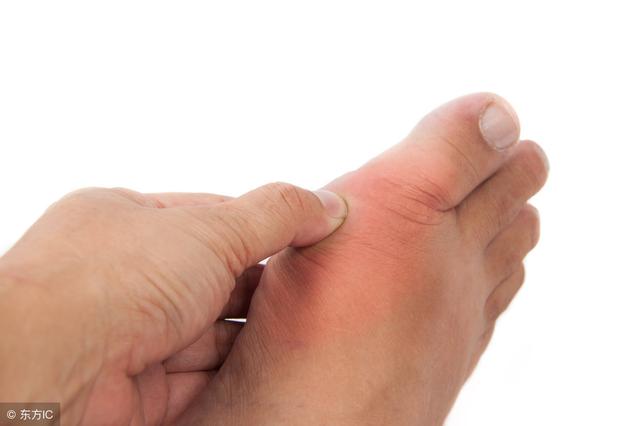

(1)痛風

痛風性關節炎發作前一定會有高尿酸血症期,但高尿酸血症不一定會發展為痛風,

從無症狀的高尿酸血症,到痛風性關節炎的首次發作需要5-10年時間;

血尿酸超過這個指標,說明離痛風更近了!

首發症狀常表現為夜間突發第一趾蹠關節疼痛難忍、局部紅腫、皮溫增高,其發病急驟,消退也快,,可在1週左右自行緩解,痛風易反復發作,可累及多個關節,並導致關節畸形。